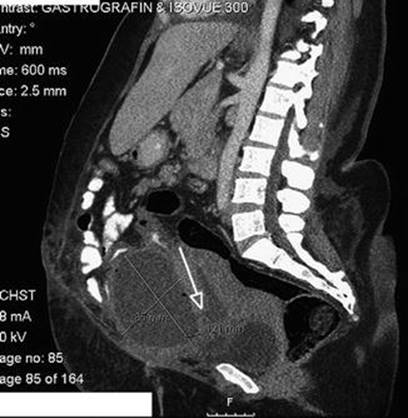

16.7.2 Abdominal CT

Abdominal CT scan should be done in unequivocal cases such as intestinal adhesions over uterine rupture delaying diagnosis. It is seen as focal disruption of the myometrium along with hemoperitoneum (Fig. 16.9). Other signs (see direct and indirect signs) such as fetal parts or hemoperitoneum outside of the uterus can be seen (Figs. 16.10, 16.11 and 16.12).

Fig. 16.11

Axial CT scan of abdomen (the same patient as in Fig. 16.10) showing the measurement of fluid collection anterior to the uterus (arrow) [209]